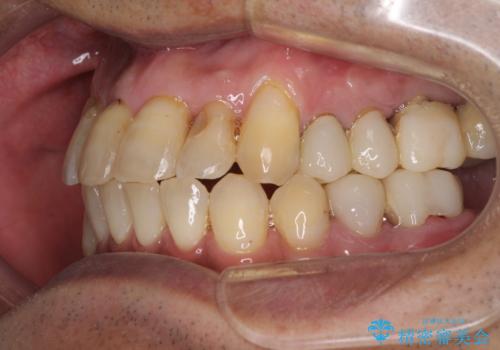

- 前歯がのデコボコや、奥歯に咬んだときに痛みがあるとのことで来院された患者様です。

全体的に問題が多く、全てをしっかりと治療したいとのことでした。

全体的に中等度の歯周病と診断されたため、歯周外科処置やインプラントによる咬合回復から進めて行き、矯正治療による歯列改善を行った後にオールセラミッククラウンにて補綴することとしました。